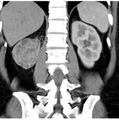

TACE 的治疗原理为通过动脉血管,在DSA 的引导下,导管选择性或超选择性插至肝脏肿瘤供血血管内,经过导管灌注化疗药物,使用栓塞剂阻塞肝脏肿瘤供血血管,使肿瘤细胞缺血、缺氧,抑制肿瘤细胞生长,促使肿瘤细胞坏死,凋亡而达到治疗目的。肝脏是人体中拥有双重血液供应系统的器官,其中肝动脉占20%~25%,另外75%~80% 来自门静脉,正常肝组织由静脉供血,而HCC血供95%以上来自动脉,因此栓塞肿瘤供血血管能够使肿瘤组织缺血坏死,而正常肝组织损伤小。